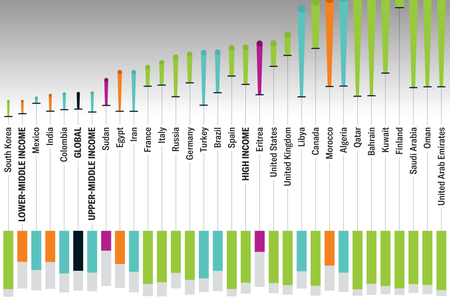

Here’s a Nuanced Look at Type 1 Diabetes Cases Worldwide

This autoimmune disease impacts millions of people worldwide, with some underserved communities bearing the brunt